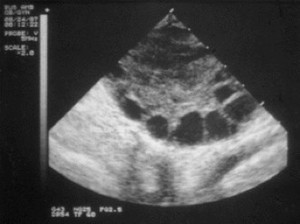

An obese 28 year-old woman goes to a fertility clinic complaining of problems of conceiving after trying for 16 months. She states she has never had regular periods. She has acne and her fasting blood sugar is elevated. An ultrasound of her uterus and ultrasound is performed and the following image is taken. What is her diagnosis and treatment?

PCOS: polycystic ovarian syndrome. The patient has cytic ovaries, hirsutism (acne), is overweight, and shows some level of insulin resistance.

7% women affected by PCOS (leading cause of infertility): see cystic follicles, atresia, and persistant anovulation; hirsutism, acne, male-pattern alopecia, obesity